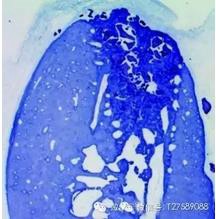

圖2:12 周后新骨形成明顯優(yōu)于未使用的牙槽嵴,LB:舌側(cè)骨,BB:頰側(cè)骨,M: 黏膜3,4

圖3:拔牙后使用Geistlich Bio-

Oss® Collagen